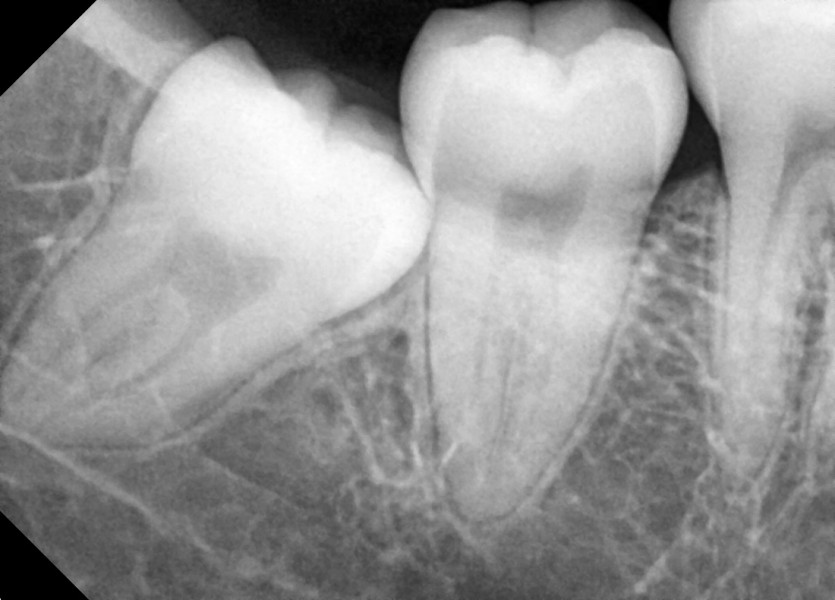

#48 사랑니 발치

구강 외과 전문의가 당일 발치했습니다.